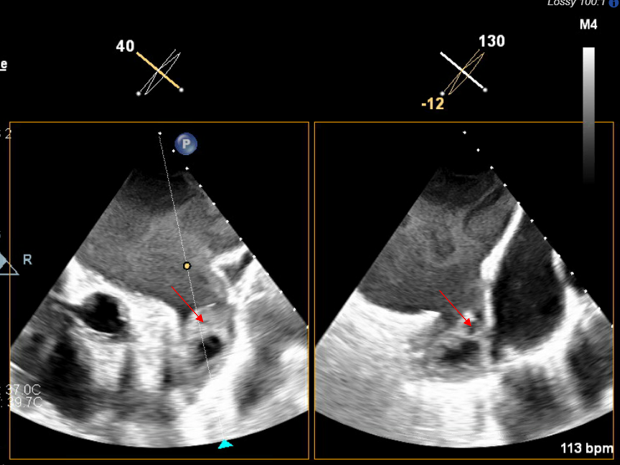

In order to prevent coronary or brain embolization of LAA thrombus, the decision was made to proceed with LAA ligation via the left thoracotomy approach. The patient was then subsequently taken to the operating room for clipping of the LAA with possible cardiopulmonary bypass only if necessary. The LAA was clipped through a left anterior thoracotomy. The patient already had access in her femoral artery and vein for possible institution of cardiopulmonary bypass should it be necessary. A large strand of thrombus was dislodged from the LAA and migrated in the left atrium, obstructing the mechanical mitral valve (Figure 2A-C). The patient was heparinized and placed on cardiopulmonary bypass.